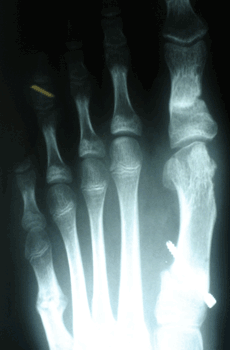

RESULTADOS

Caso 1: Hallux Valgus del adolescente